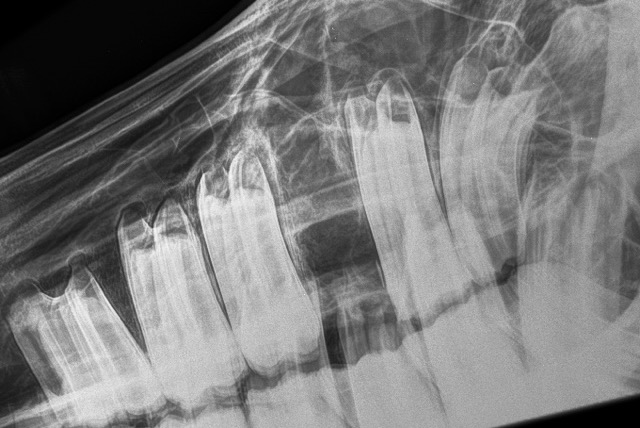

In this prospective study, the prevalence of bacteraemia in horses following tooth extraction and bacterial species involved was documented in 20 horses presented with dental disease to a single facility in Germany. Half underwent cheek tooth extraction and the other half underwent canine or incisor extraction. Oral extraction under sedation and local anaesthesia was performed in a standard manner.

Blood samples for culture were obtained immediately after catheter placement and at 1, 5 and 20 minutes after the first gingival incision and then every 30 minutes thereafter until the tooth was extracted. At each sampling point the surgical activity was recorded. Blood and swabs from extracted teeth were cultured under aerobic, anaerobic and microphilic conditions. Horses’ temperatures were recorded every 3 hours until 48 hours post-operatively.